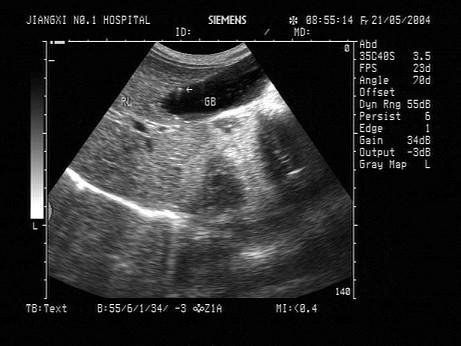

问题 女,28岁,无任何不适,体检。声像图如图所示,诊断为?(?)

选项 A.胆囊结石 B.胆囊息肉 C.胆囊胆固醇结晶 D.胆囊腺瘤 E.胆囊癌

答案 C